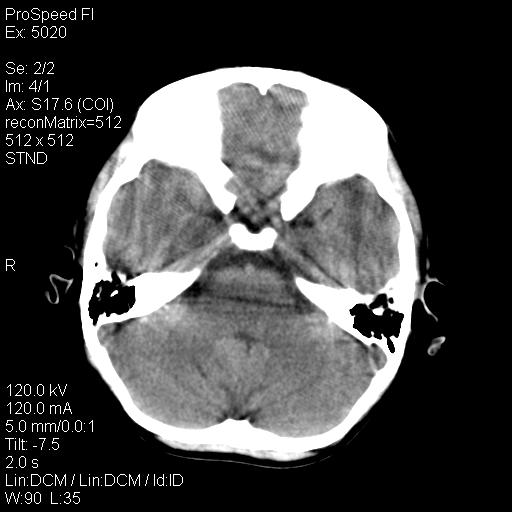

标题: PED1637:M 6Y 顶部无痛性包块两月。 [打印本页]

标题: PED1637:M 6Y 顶部无痛性包块两月。

2、颅骨局部缺失,边缘光滑、整齐

颅骨的病损表现为内外颅骨板层不规则的锋利的破坏,形成“斜边缘”,有一定的特点

颅骨为好发部位,生长缓慢,常位于顶骨、枕骨及颞骨,表现为颅骨缺损,呈圆形或椭圆形,边界清,无硬化

事发冠状缝与矢状缝交界区,密度较低,考虑表皮样囊肿可能性大,其次不除外嗜酸性肉芽肿